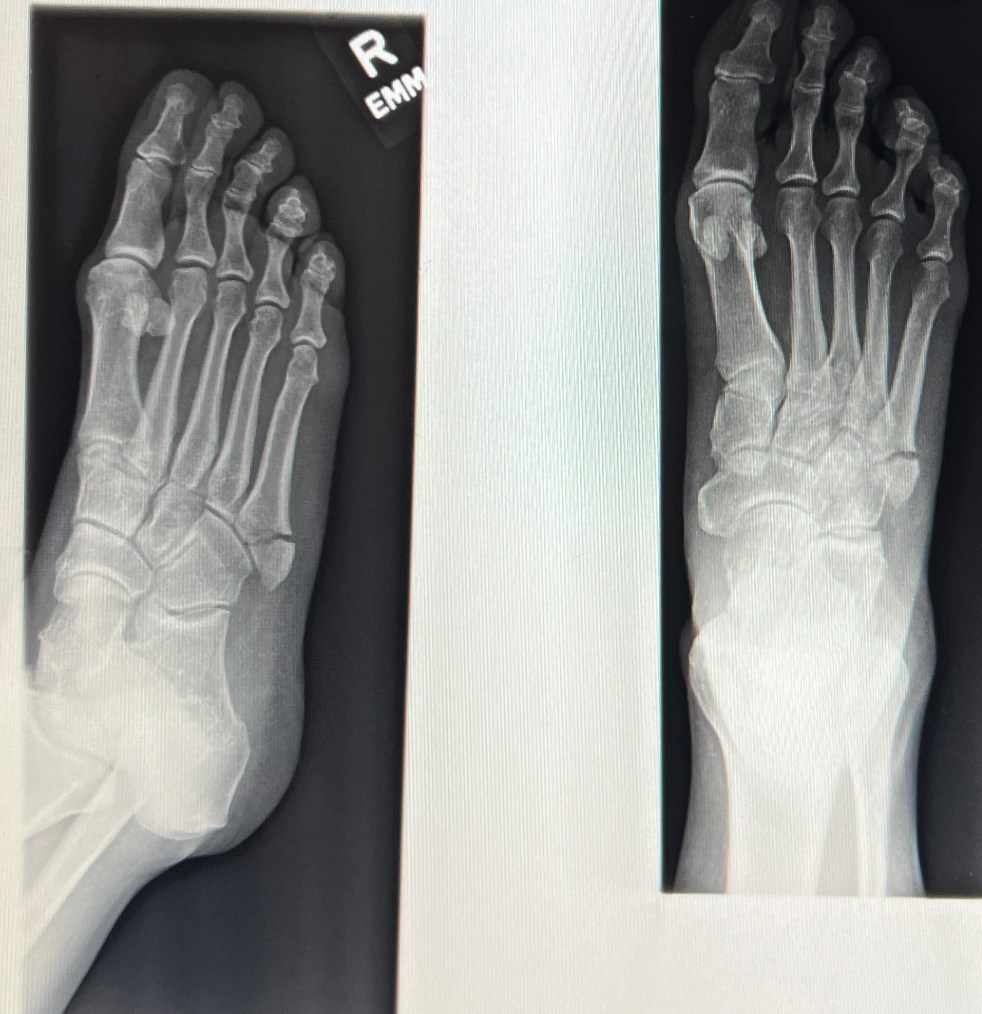

Sometimes you break yourself, part 8

I'm approaching the end of week seven post-fifth metatarsal break and the foot is healing, slowly but surely. My follow-up appointment was on Friday morning, just two days before the end of the seven-week mark. Another set of X-Rays were taken and unfortunately, it didn't look that much different from the one taken the week… Continue reading Sometimes you break yourself, part 8